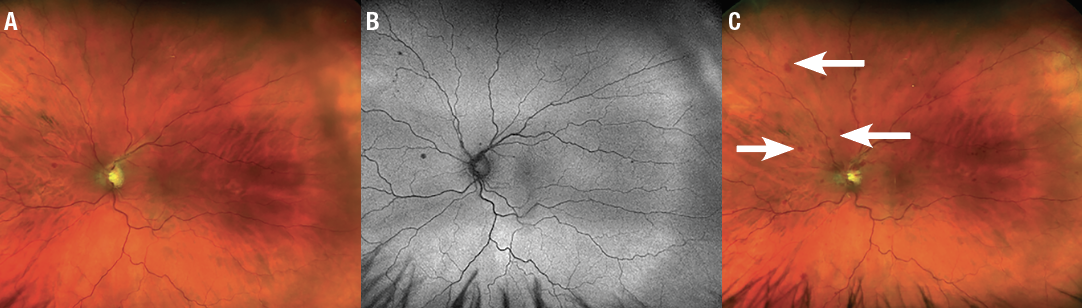

The dilated fundus exam of the right eye revealed collaterals and mild pallor of the disc. The macula was noted to have pigmentary changes, focal laser scars and temporal blot heme. These findings were all consistent with the patient’s history of CRVO after focal laser treatment in the right eye and unchanged from his visit six months earlier. Color fundus photos and fundus autofluoresence in the left eye (Figure 1) demonstrated blot hemorrhages in the superior retina and a tortuous venous system throughout.

| Figure 1. A) Fundus photography of the left eye shows blot hemorrhages of the superior hemiretina as well as a tortuous venous system. B) Fundus autofluorescence of the eye highlights the blot hemorrhages in the superior retina. C) Fundus photography of the left eye two weeks after the initial visit shows increased blot hemorrhages (arrows) now involving the entire retina and a new flame hemorrhage off the optic nerve superotemporally. |

Two weeks later, he restarted warfarin and his prothrombrin time (PT) was back within goal at 2.4. VA remained 20/20, but subjectively his vision had worsened and on exam he showed increased blot hemorrhages now spreading to involve the entire retina and a new flame hemorrhage off the optic nerve (Figure 1C). OCT remained stable without macular edema. We-added another nonprostaglandin IOP-lowering agent because his IOP stabilized at 14 mmHg.